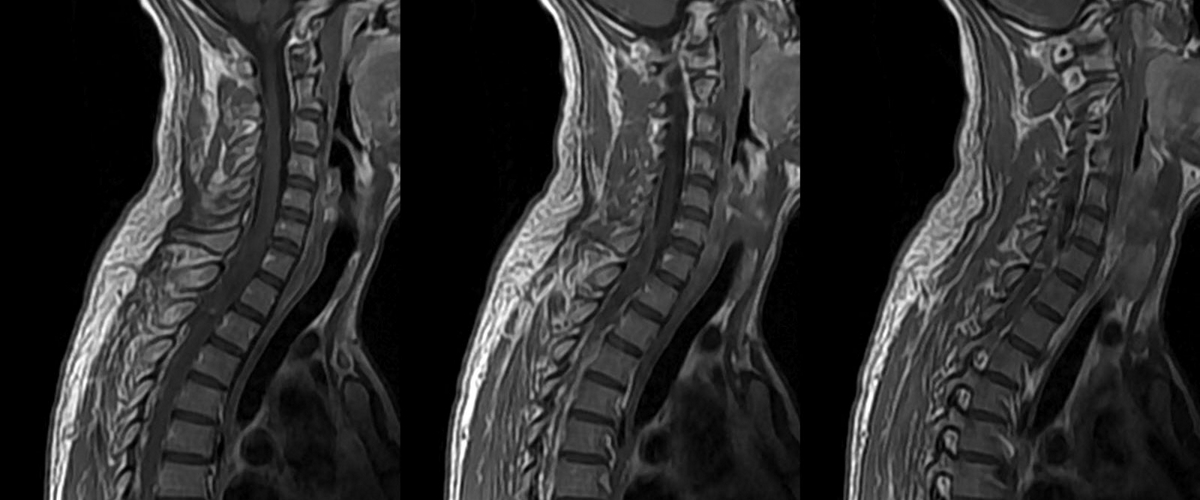

Как вернуть движение: технологии для восстановления после травм позвоночника

Представьте, что тонкая нить вашего спинного мозга — это скоростная магистраль, по которой мчатся электрические импульсы от мозга к мышцам. Серьёзная травма — и дорога разрушена. Связь потеряна. К сожалению, наше тело не умеет чинить такие сложные «провода». Но что, если мы построим умный мост в обход разрушения? Именно над этим сейчас бьются лучшие умы.

В основе системы — специальный имплант. Его вживят добровольцам, и он станет личным переводчиком и курьером для нервных сигналов, ловя их и отправляя в обход повреждённого участка спинного мозга. Гениальная идея, не правда ли?